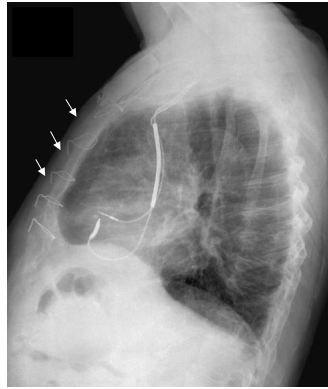

Observe a figura abaixo.

As setas indicam